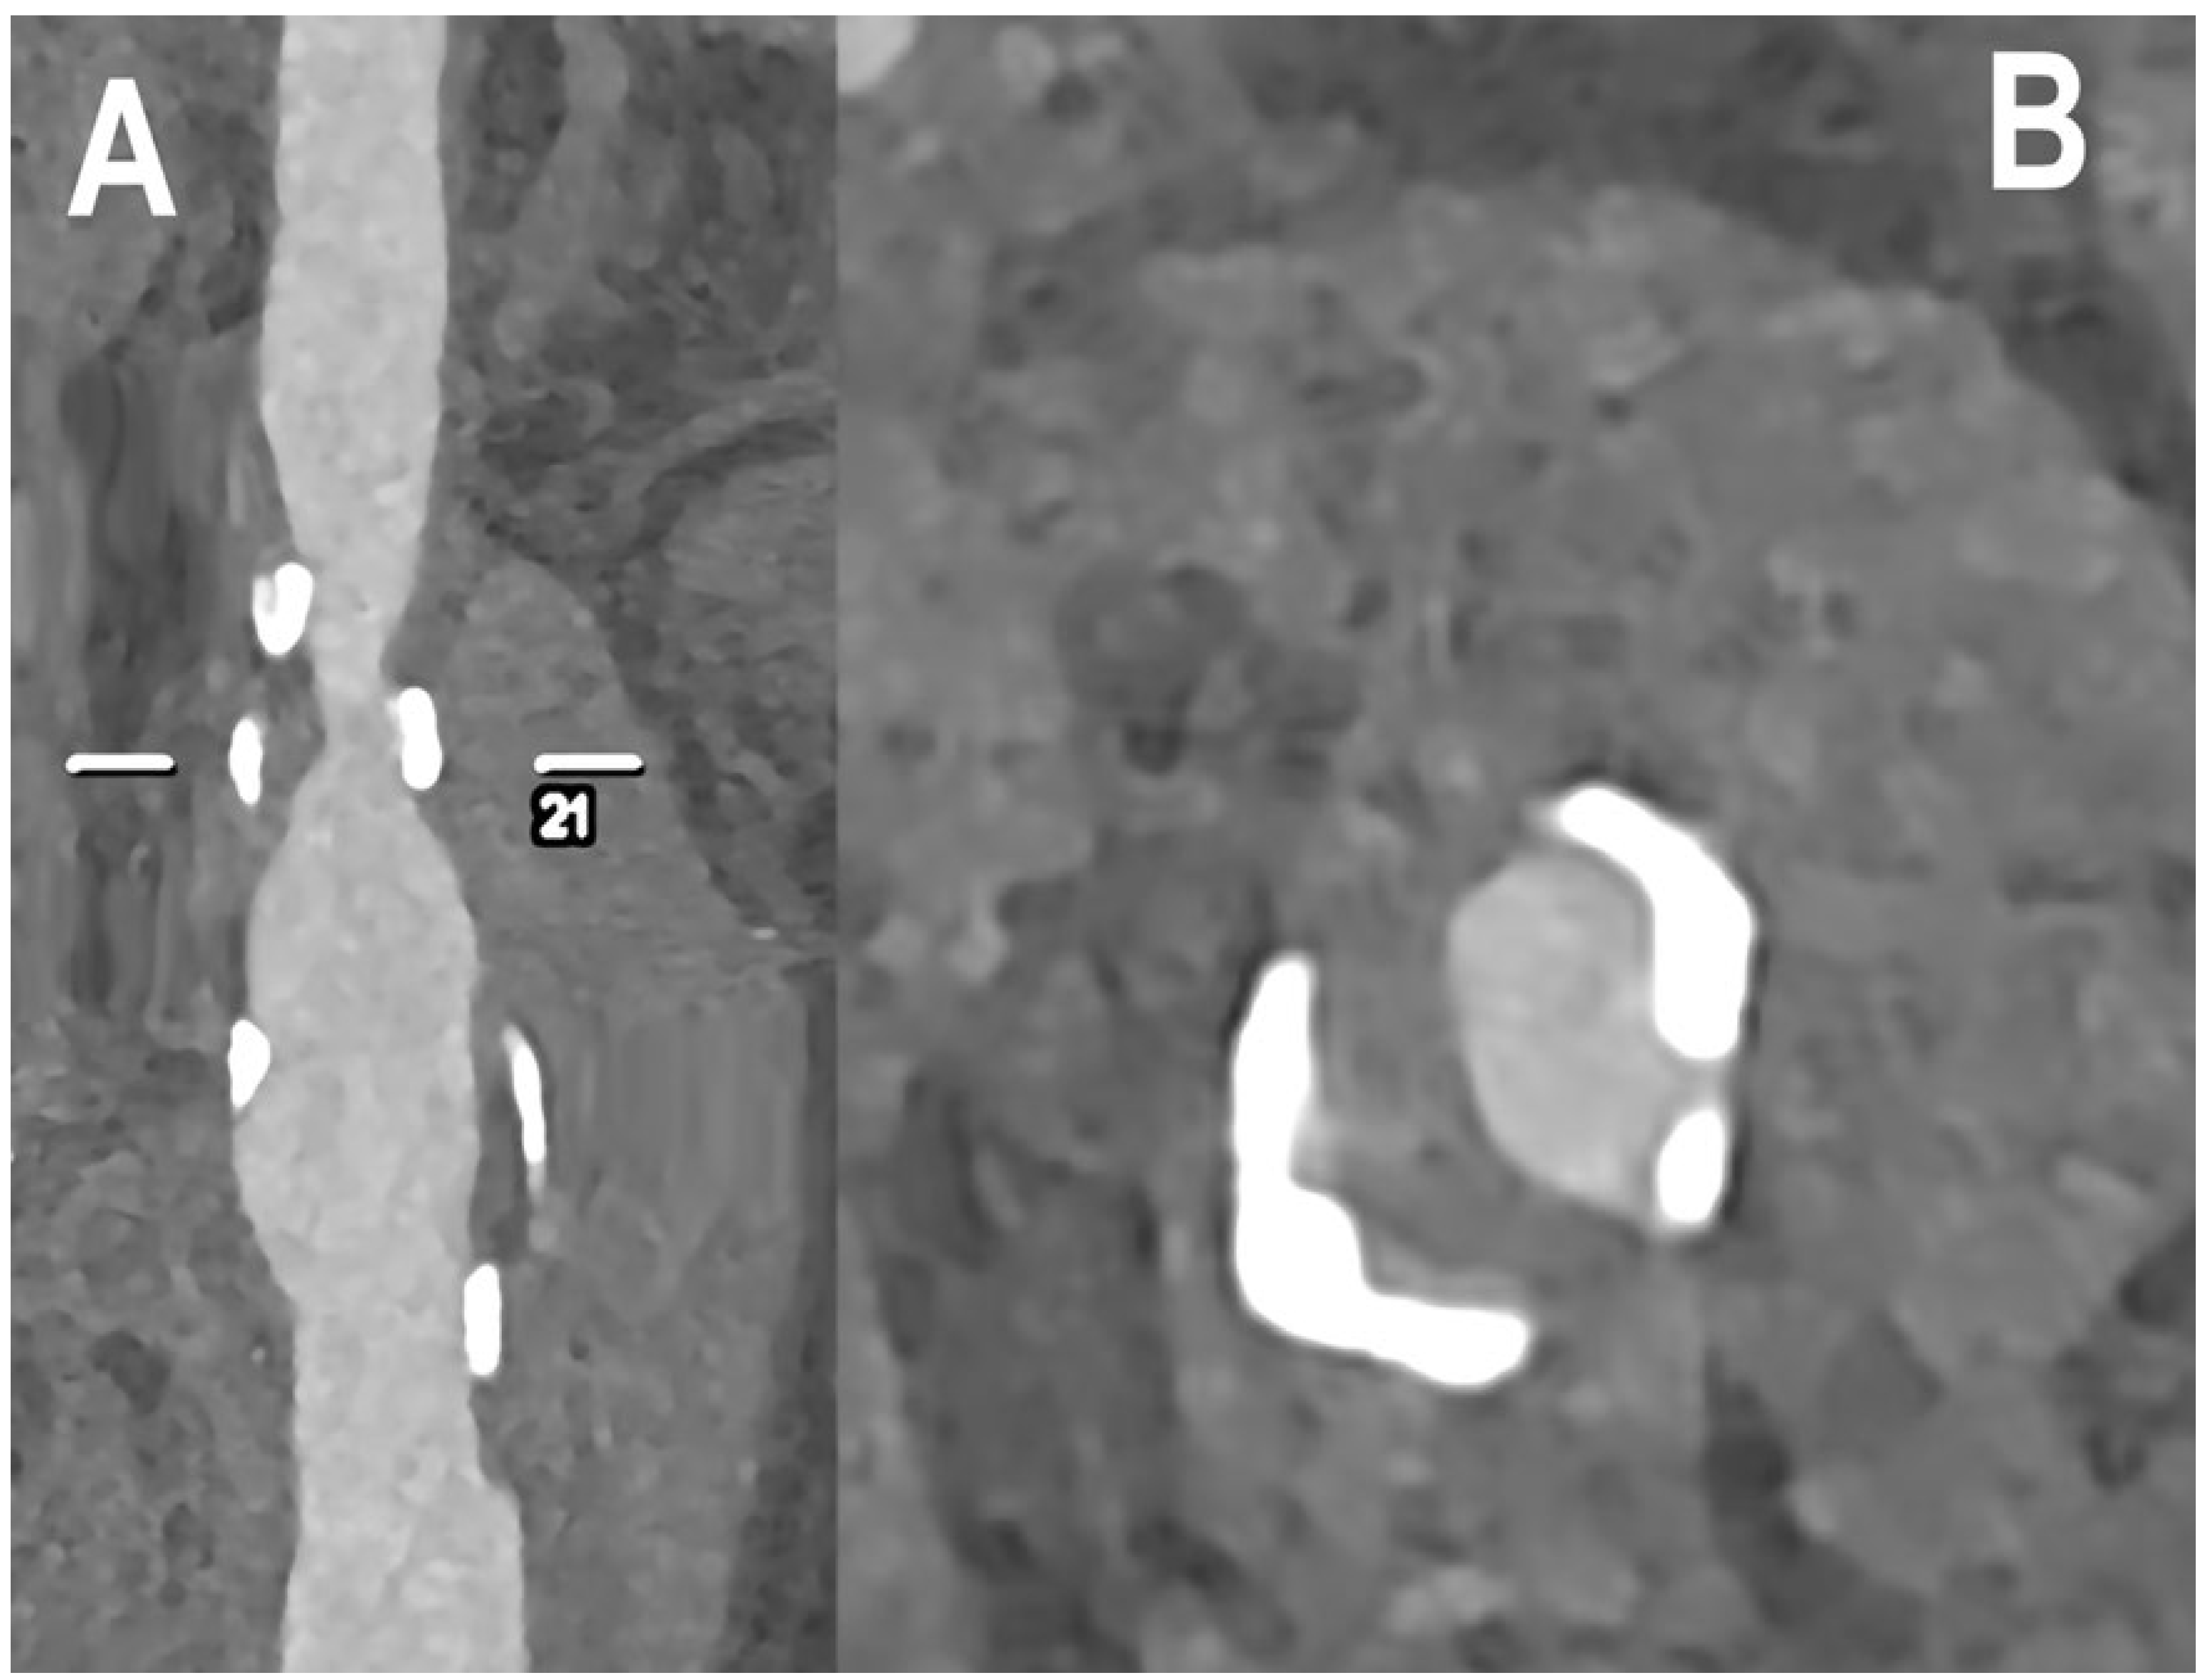

| Pourmorteza et al. [32] | 2017 | Ex vivo In vivo (human) | 21 | Increased resolution | Ex vivo, PCCT images showed 8.5 ± 4.8% less image noise than EID images. In vivo, PCD image-quality scores were significantly better for GM–WM differentiation and image noise (both p < 0.001). In the quantitative image analysis, PCCT performed better than EID-CT for image noise, SNR of GM, WM and lateral ventricle CSF, and GM–WM contrast. In the spectral analysis, GM–WM contrast was better for the low-energy bin rather than the high-energy bin, whereas the image noise was higher in each bin than in PCD images containing all detected photons. |